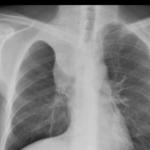

Sarcoid

Album: Sarcoid